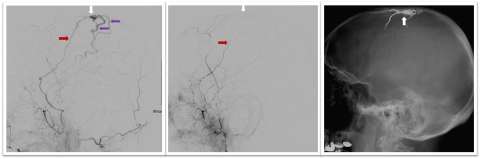

Panel of images showing skull x-ray and Dural Arteriovenous Fistula Embolization

Figure 1. Dural Arteriovenous Fistula Embolization - Lateral or side view (left panel) of a dura matter artery (red arrow) abnormally connecting to veins in the dura matter (white arrow), and high-pressure arterial flow is immediately filling

• Endovascular liquid embolization: This minimally invasive technique is performed by inserting a catheter through the groin (or other vessel), then injecting a liquid that solidifies in the blood vessel and cuts off blood flow to the fistula. The cerebrovascular team at UCLA is actively involved in research and testing of new liquid embolic treatments (Figures 1-2). This is the most common method of treating DAVF, and it is often curative.

• Coil embolization: Micro-coils made of platinum are placed into the artery, vein or venous sinus to seal off the DAVF abnormal connection and prevent blood flow through it.